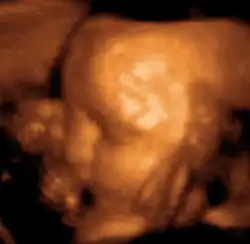

Sonogram of a fetus at 14 weeks (profile)

Head of a fetus, aged 29 weeks, in a "3D ultrasound"

The potential for ultrasonic imaging of objects, in which a 3 GHz sound wave could produce resolution comparable to an optical image, was recognized by Sergei Sokolov in 1939. Such frequencies were not possible at the time, and what technology did exist produced relatively low-contrast images with poor sensitivity.[36] Ultrasonic imaging uses frequencies of 2 megahertz and higher; the shorter wavelength allows resolution of small internal details in structures and tissues. The power density is generally less than 1 watt per square centimetre to avoid heating and cavitation effects in the object under examination.[37] Ultrasonic imaging applications include industrial nondestructive testing, quality control and medical uses.[36]

Medical ultrasound is an ultrasound-based diagnostic medical imaging technique used to visualize muscles, tendons, and many internal organs to capture their size, structure and any pathological lesions with real time tomographic images. Ultrasound has been used by radiologists and sonographers to image the human body for at least 50 years and has become a widely used diagnostic tool.[38] The technology is relatively inexpensive and portable, especially when compared with other techniques, such as magnetic resonance imaging (MRI) and computed tomography (CT). Ultrasound is also used to visualize fetuses during routine and emergency prenatal care. Such diagnostic applications used during pregnancy are referred to as obstetric sonography. As currently applied in the medical field, properly performed ultrasound poses no known risks to the patient.[39] Sonography does not use ionizing radiation, and the power levels used for imaging are too low to cause adverse heating or pressure effects in tissue.[40][41] Although the long-term effects due to ultrasound exposure at diagnostic intensity are still unknown,[42] currently most doctors feel that the benefits to patients outweigh the risks.[43] The ALARA (As Low As Reasonably Achievable) principle has been advocated for an ultrasound examination – that is, keeping the scanning time and power settings as low as possible but consistent with diagnostic imaging – and that by that principle nonmedical uses, which by definition are not necessary, are actively discouraged.[44]